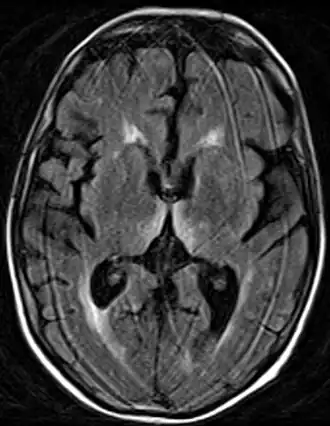

| Lesão no diencéfalo, especificamente no núcleo dorsomedial do tálamo e nos corpos mamilares. | |

A síndrome de Korsakoff é atribuída a uma lesão no diencéfalo, especificamente no núcleo dorsomedial do tálamo e nos corpos mamilares, que, como vistos, são essenciais na construção da memória, o que causaria a amnésia anterógrada. Para agravar esse quadro ocorre também atrofia cortical generalizada, afetando especialmente o lobo frontal e temporal. Essa lesão no córtex cerebral seria a responsável pela amnésia retrógrada e até mesmo uma complicação à já existente questão da identidade, sendo que o lobo frontal tem enorme importância na formação da personalidade e na integração de inúmeras informações corticais.[4]